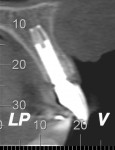

When the patient was 18 years old, root fracture of tooth No. 8 occurred, which was an indication for extraction (Figure 1 and Figure 2). Six months later, tooth No. 9 was also designated for extraction due to recurrent periapical lesions (Figure 4 and Figure 5). The following treatment plan was established: extraction of teeth Nos. 8 and 9 and performance of IDR at two different times (Figure 3 through Figure 11); placement of two ceramic abutments and all-ceramic crowns (Figure 12 through Figure 15); and continued orthodontic treatment to finalize the case.

The same procedure was used for tooth No. 9. Six months after the second procedure, definitive restorations fabricated from zirconia-ceramic were placed for both central incisors. The patient was clinically and radiographically followed every 6 months. Figure 12 through Figure 15 show the occlusal and buccal clinical aspect at 3 years follow-up, and Figure 16 and Figure 17 show the tomographic follow-up of the buccal plate bone.